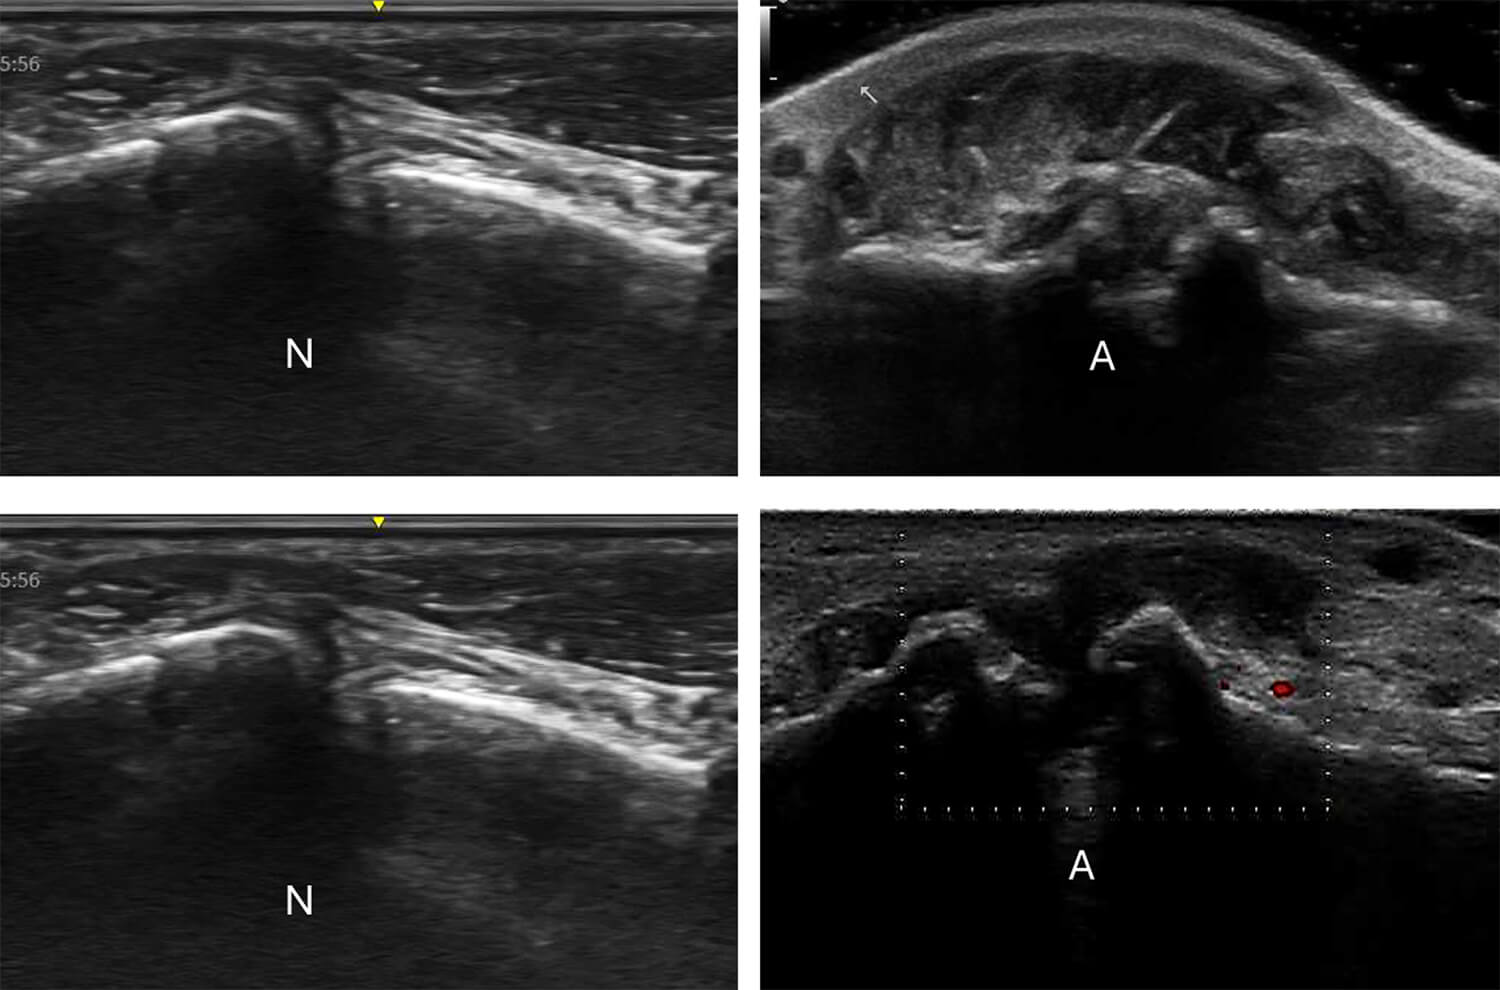

Twee voorbeelden van echografie van artrose, met links (N) een normaal gewricht en rechts (A) een gewricht met artrose.

Terwijl röntgenfoto's voornamelijk structurele veranderingen zoals gewrichtsruimteversmalling en osteofyten in een later stadium van de ziekte kunnen detecteren, maakt echografie het mogelijk om zowel vroege als late veranderingen in het gewricht te visualiseren.

Echografie kan subtiele afwijkingen in het kraakbeen, zoals vervaging van de randen en verlies van homogeniteit, al in een vroeg stadium identificeren.

Bovendien kan echografie actieve ontstekingen detecteren door middel van Doppler-technieken, die een verhoogde vasculaire activiteit in het synoviale weefsel aantonen. Dit is een cruciaal voordeel, aangezien het de mogelijkheid biedt om te beoordelen of de artrose momenteel ontstoken is, wat niet mogelijk is met röntgenfoto's.